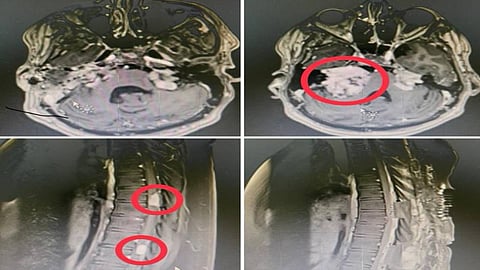

نجح فريق طبي تكاملي بمدينة الملك عبدالله الطبية بالعاصمة المقدسة، عضو تجمع مكة المكرمة الصحي ممثلاً بمركز العلوم العصبية، من استئصال ورم ليفي عصبي ضخم في قاع الجمجمة ضاغطاً على جذع الدماغ, بالإضافة إلى ورمين آخرين أحدهما سحائي والأخر ليفي ضاغطين على الحبل الشوكي لشاب في العقد الثاني في عملية نادره وعالية الخطورة.

وأوضح قائد الفريق الطبي الدكتور محمد غازي عبده، أن صعوبة العملية تكمن في تعدد الأورام في أماكن خطيرة وملاصقة لجذع وأعصاب الدماغ والحبل الشوكي, حيث تم تجهيز خطة جراحية من مرحلتين لاستئصال الأورام الكبيرة والمؤثرة على المريض وتم في المرحلة الأولى إزالة الورم الليفي العصبي الملاصق لجذع الدماغ تحت المراقبة العصبية، وباستخدام جهاز الملاحة الجراحية والميكروسكوب الجراحي، في عملية استغرقت تسع ساعات, وفي المرحلة الثانية قام الفريق بتدخل جراحي ثاني للورمين الضاغطين على الحبل الشوكي واستخدام الميكروسكوب الجراحي استغرقت ست ساعات التي أوضحت نتائجها وجود ورمين من نوعين مختلفين أحدهما سحائي والأخر ليفي.